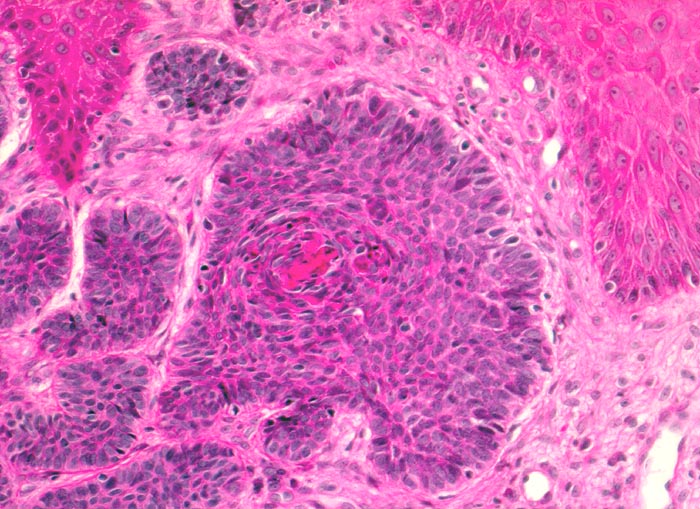

Morphologische Merkmale:

• Fokale oberflächliche Ulzeration bzw. Erosion der Epidermis über dem Tumor.

• Solide blaue Tumorzellplatten in der Dermis, teils mit Kontakt zur Epidermis.

• Die zytoplasmaarmen Tumorzellen ähneln Basalzellen der Epidermis.

• Palisadenförmige Anordnung der Tumorzellen am Rand der Zellplatten.

• Retraktionsartefakt zwischen Tumor und Stroma.

• Tumorstroma bestehend aus Fibroblasten, lockeren Kollagenfasern, hellblauen Muzineinlagerungen und chronischem Entzündungsinfiltrat.

• Im Zentrum einzelner Tumorzellplatten Verhornung, Tumornekrosen oder Hohlraumbildungen.